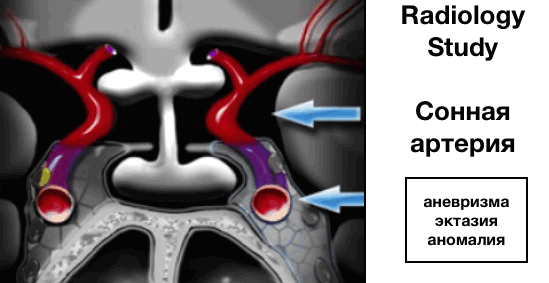

Внутренняя сонная артерия (ВСА)

Далее оцениваются внутренние сонные артерии, которые имеют сложный анатомический ход, проходя сперва через основание черепа, визуализируясь в виде буквы S на боковых срезах, а далее через кавернозные синусы.

Краниальные сегменты ВСА также называют супракавернозными сегменты.

ВСА бифуркируется на ветви:

- передней мозговой артерии (ПМА), проходящие вдоль перекреста зрительных нервов

- средней мозговой артерии (СМА), проходящие латеральнее.

Наиболее частые патологии:

- аневризма

- эктазия

- аномалия развития сосудов, в том числе медиальное расположение ВСА (практически по медиальной линии).